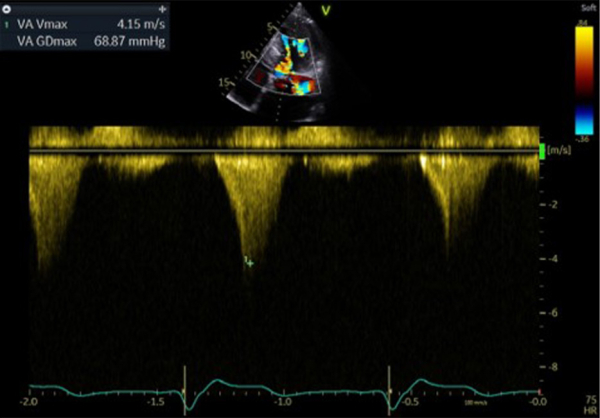

Figure 2 : flux Doppler continu trans-aortique d’obstruction

Figure 3 : flux Doppler continu trans-mitrale d’IM

Figure 4 : superposition des 2 flux Doppler continu d’obstruction sous aortique et d’IM

- Patient de 40 ans avec une CMH sarcomérique (mutation HTZ MYBPC3) avec épaisseur maximale en antéro-septo-basal à 33mm en IRM, associée à une obstruction sous aortique significative (GD max 77 mm Hg au Valsalva). Découverte d’une insuffisance mitrale (IM) sévère mixte organique sur prolapsus de P2 et fonctionnelle sur un SAM (mouvement systolique antérieur de la valve mitrale)

Figure 5 : flux Doppler continu trans-aortique

Il s’agissait d’une hémolyse mécanique en lien avec l’obstruction sous aortique (Gradient max 68 mm Hg) favorisée par un SAM de la valve mitrale à l’origine de la persistance d’une IM de haut grade. On suspectait notamment un SAM de néo cordage. Un contact direct entre hématies et anneau prothétique à l’origine d’un stress mécanique est possible aussi mais plus anecdotique.